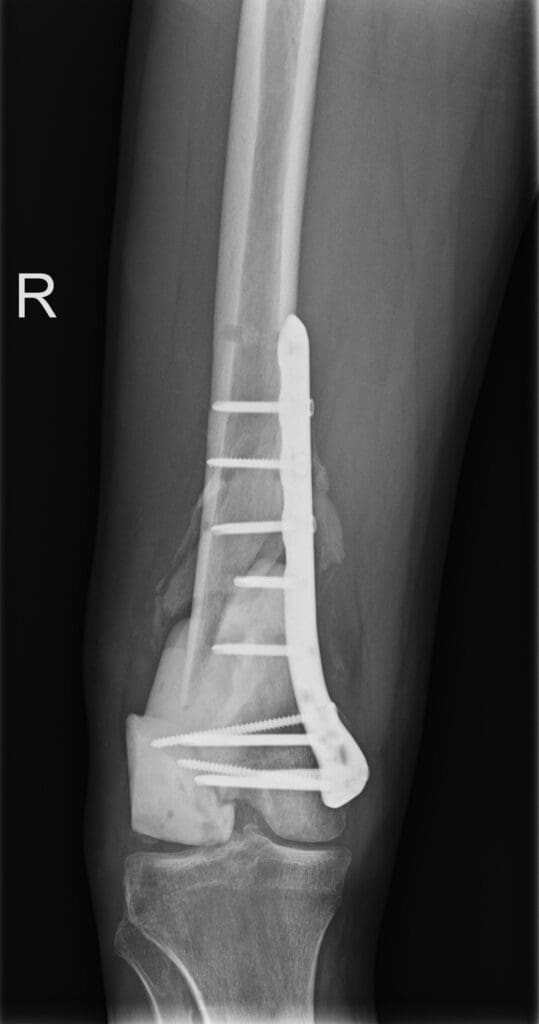

Młody mężczyzna trafił do szpitala w stanie skrajnie ciężkim. W wyniku wypadku doznał m.in. odmy opłucnowej, złamań otwartych oraz licznych urazów tkanek miękkich. Jego życie przez wiele dni podtrzymywała aparatura wspomagająca oddychanie. Lekarze natychmiast podjęli działania ratujące zdrowie pacjenta – konieczne było przeprowadzenie drenażu opłucnej oraz zabezpieczenie złamań przy użyciu stabilizatorów zewnętrznych.

Po ustabilizowaniu najgroźniejszych obrażeń konieczne było przeprowadzenie kilku poważnych operacji ortopedycznych. Jednym z najtrudniejszych wyzwań było zrekonstruowanie kolana, które w wyniku wypadku uległo niemal całkowitemu zniszczeniu. Fragmenty kości uległy martwicy i rozpadowi, co znacząco utrudniało możliwości dalszego leczenia.